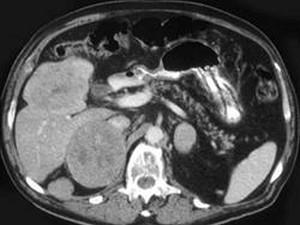

问题 男性,60岁,曾患乙肝,肝硬化多年,右上腹胀痛1月余,AFP为80.8μg/L,CT检查如图所示,最佳的诊断是 ( )

选项 A.肝结节性增生、右肾上腺瘤 B.肝、右肾上腺均为转移瘤 C.肝癌右肾上腺转移 D.肝腺瘤、右肾上腺腺瘤 E.肾上腺癌肝转移

答案 C